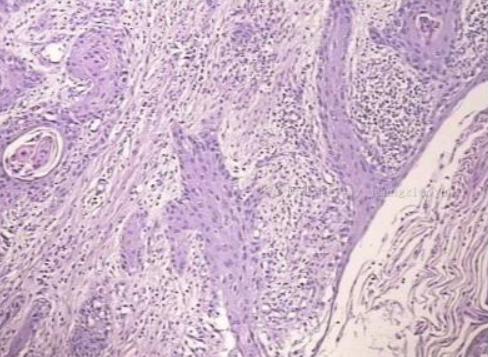

别小看了外阴阴道,这里可以导致女性瘙痒难忍的原因可谓多多,比如炎症(外阴阴道假丝酵母菌病、细菌性阴道炎、滴虫性阴道炎以及混合性阴道炎等)、外阴非上皮内瘤变(HPV感染引起和非HPV感染引起)、外阴皮肤病(外阴湿疹、硬化性苔藓、单纯性苔藓、扁平苔藓等)、肿瘤(外阴癌)。

除了孩子,老年患者也会深深触动我,很多老人直到痒得受不了或者长出肿块来才告诉家人,有的不好意思告诉儿子,拖了很久才告诉媳妇,每每看到这样的情景,我就希望所有这样的老年患者都能早点了解医学知识,不要小病拖成大病。比如外阴上皮内瘤变和硬化性苔藓,不及时规范治疗的话若干年后会进展为外阴鳞癌,而事实上,这些疾病在早期完全是有办法及时阻断治疗的。